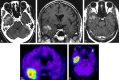

CNS lymphoma consists of 2 major subtypes: secondary CNS involvement by systemic lymphoma and PCNSL. Contrast-enhanced MR imaging is the method of choice for detecting CNS lymphoma. In leptomeningeal CNS lymphoma, representing two-thirds of secondary CNS lymphomas, imaging typically shows leptomeningeal, subependymal, dural, or cranial nerve enhancement. Single or multiple periventricular and/or superficial contrast-enhancing lesions are characteristic of parenchymal CNS lymphoma, representing one-third of secondary CNS lymphomas and almost 100% of PCNSLs. New CT and MR imaging techniques and metabolic imaging have demonstrated characteristic findings in CNS lymphoma, aiding in its differentiation from other CNS lesions. Advanced imaging techniques may, in the future, substantially improve the diagnostic accuracy of imaging, ultimately facilitating a noninvasive method of diagnosis. Furthermore, these imaging techniques may play a pivotal role in planning targeted therapies, prognostication, and monitoring treatment response.